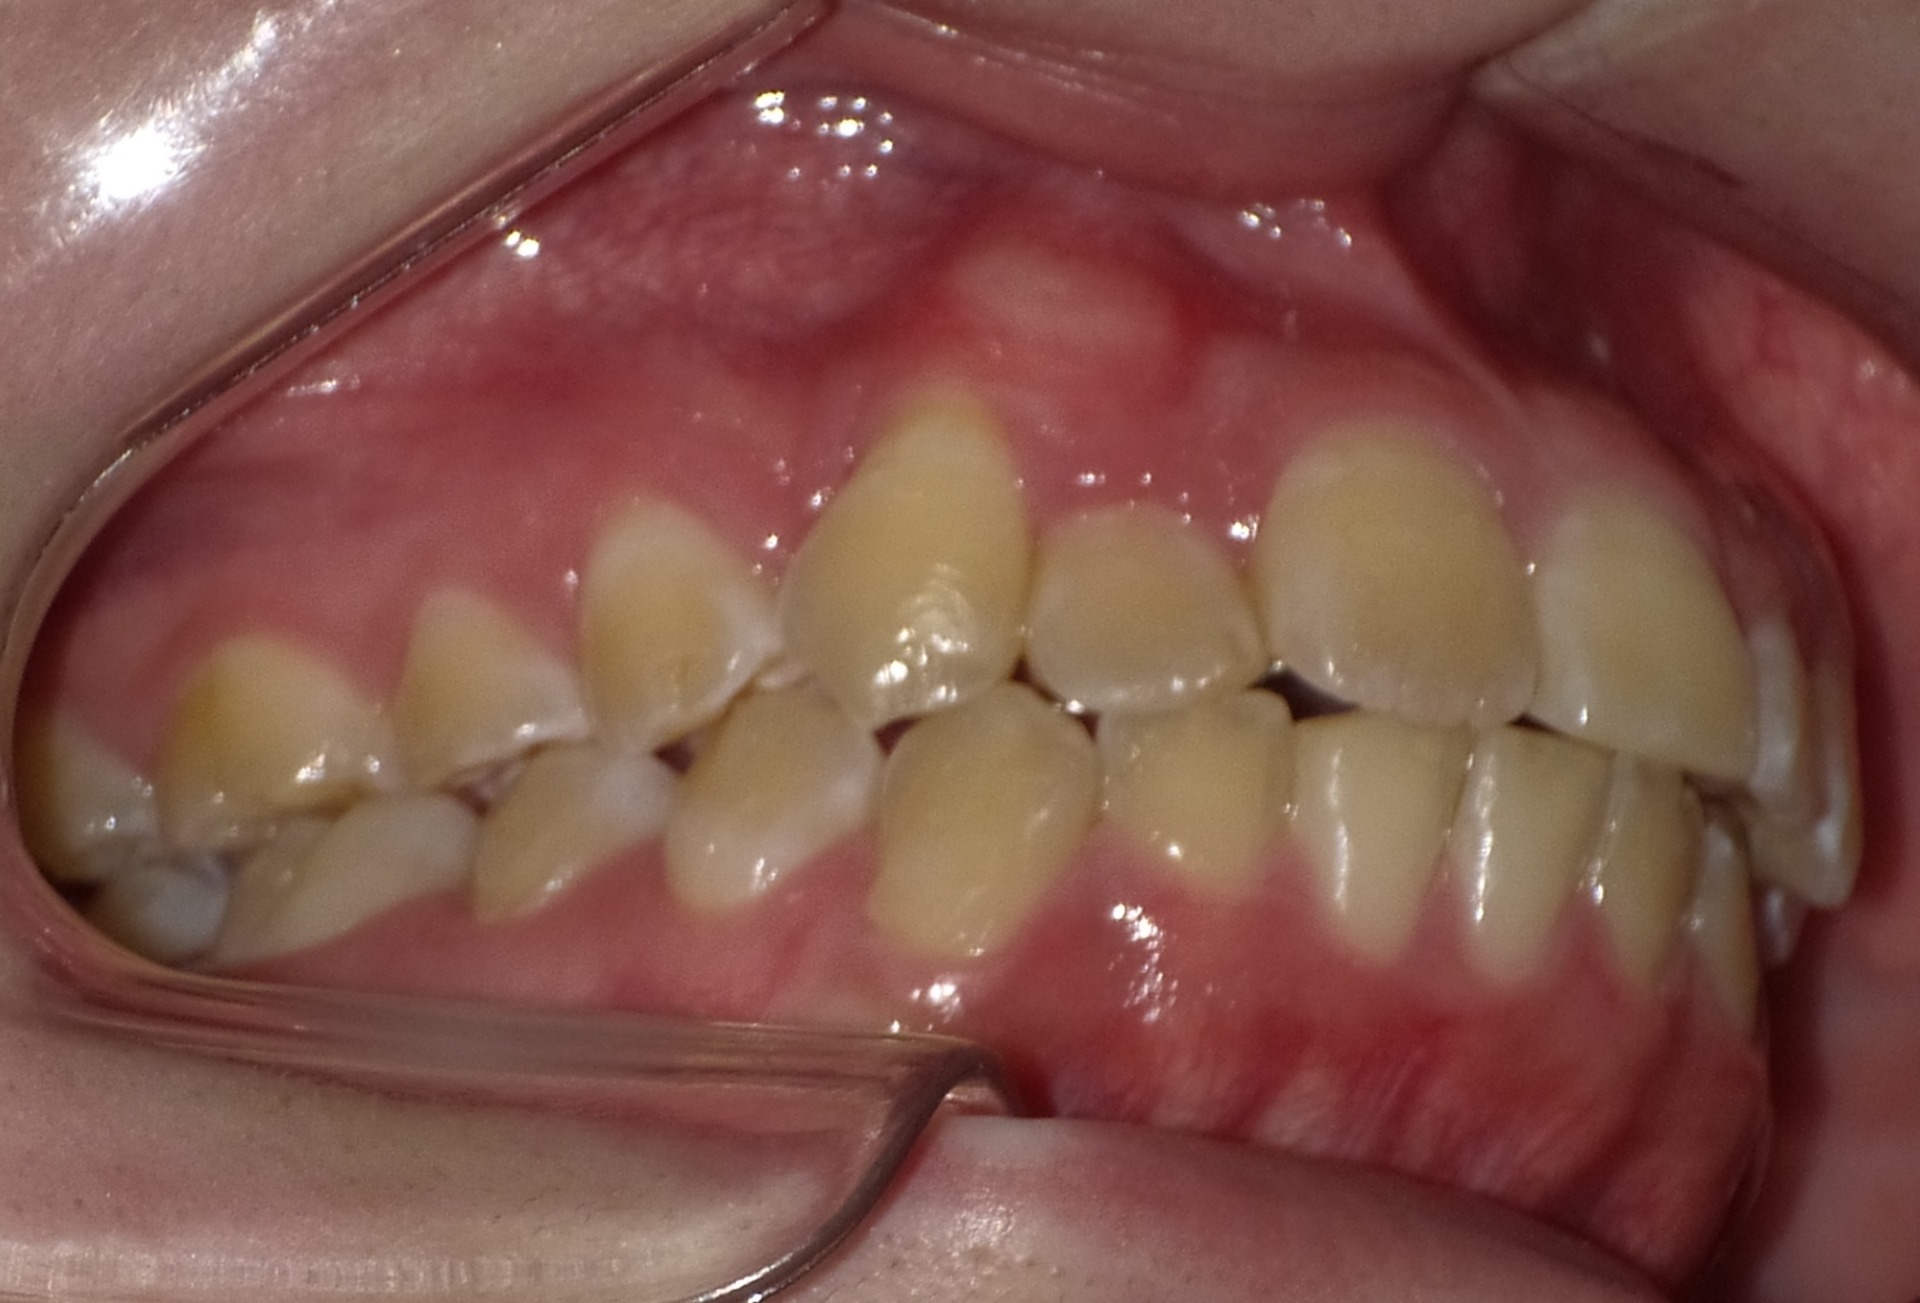

矯正後

| 症状 | 左上2番3番逆転症例 |